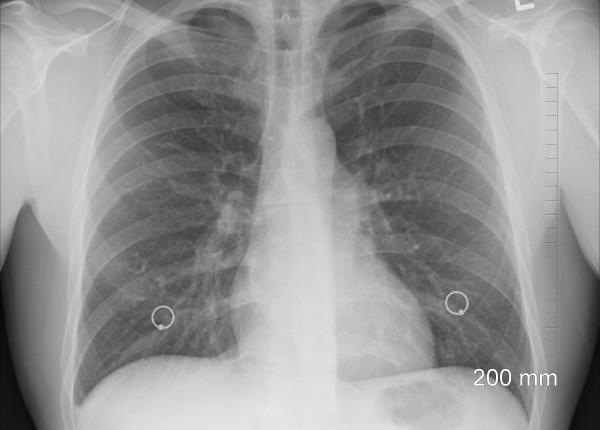

Prof. dr. Emanoil Ceaușu, reputat specialist în Boli Infecțioase, a vorbit, luni, 5 aprilie, la Academia de Sănătate, despre pandemia de coronavirus și a descifrat lucrurile cele mai importante...